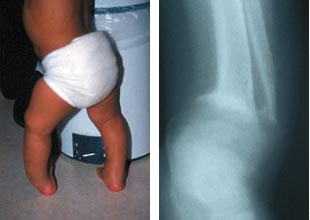

Vitamin D-mangel er også utbredt blant enkelte grupper innvandrerbarn i Norge (28, 29). Det er sannsynlig at vitamin D-status blir dårligere etter migrasjon, selv om det også i de aktuelle gruppenes hjemland er relativt vanlig med vitamin D-mangel (30 – 32). Spesielle risikogrupper ser ut til å være:

Det finnes ingen gode epidemiologiske studier som mer presist dokumenterer forekomsten av rakitt blant barn i Norge. De fleste barn med denne diagnosen vil bli utredet og behandlet av en spesialist i barnesykdommer, som regel i tilknytning til en poliklinisk utredning eller en innleggelse ved en somatisk barneavdeling. Det foreligger ingen innrapportering av barn med rakitt til noe sentralt register. For å få en oversikt over problemets omfang sendte vi et spørreskjema til alle landets barneavdelinger i januar 2000, der vi spurte etter hvor mange tilfeller med rakitt som var behandlet ved den aktuelle enhet i løpet av 1998 og 1999. 25 av 30 barneavdelinger svarte. Disse dekker> 95 % av den norske barnepopulasjonen. 65 barn med ernæringsbetinget rakitt ble registrert. 54 av barna hadde innvandrerbakgrunn (begge foreldre født i utlandet). 20 barn hadde bakgrunn fra Pakistan. 18 av disse barna kom fra Oslo, og det representerer ca. 50 % av barna som ble behandlet for rakitt i Oslo i perioden. Øvrige nasjoner som var representert var Marokko, Irak, Iran, Tyrkia, Bosnia, Madagaskar, Somalia, Kosovo, Sri Lanka, Albania, Korea og Libanon. Foreldrenes trosoppfatning ble ikke registrert. 23 barn var under ett år, 28 barn mellom ett og to år og 14 barn mer enn to år. Tallene tyder på at alimentær rakitt ikke er uvanlig i Norge, og at det er behov for å bedre det forebyggende arbeidet på dette området.